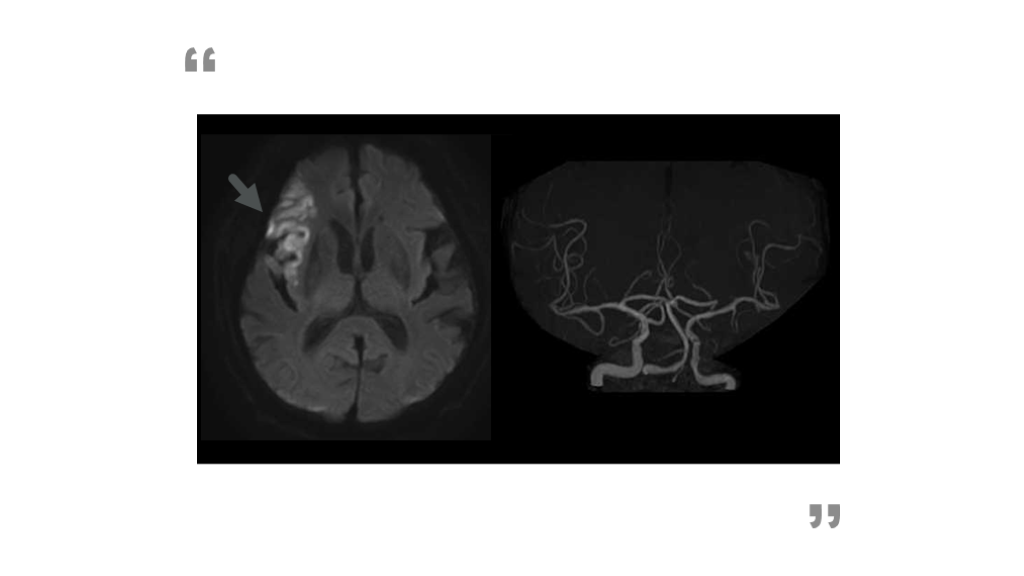

23時頃バタンと音がしたので家人が見に行くと床に倒れていた。意識障害、右片麻痺あり。救急搬送。既往は慢性心不全。初診時所見は眼球は左共同偏倚、自発語なし、失語あり。右片麻痺は完全であった。 症例でまとめ 81歳女性、意識障害

発症機序:塞栓性機序(突発発症) 皮質症状あり 主幹動脈閉塞うたがい  ➡心原性脳塞栓症S/O